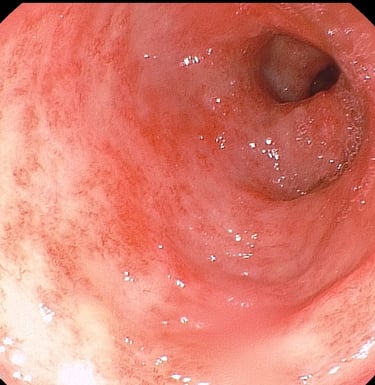

Tumores gástricos

Úlcera gástrica con hemorragia activa